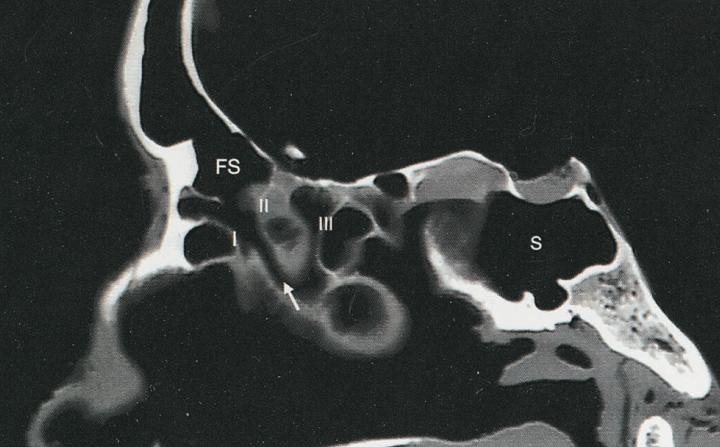

Abbildung

Der Ductus frontonasalis kann in einer CT-Bildgebung dargestellt werden.